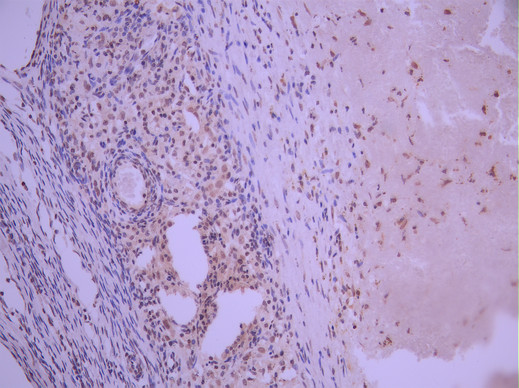

IHC image of CSB-RA209742A0HU diluted at 1:100 and staining in paraffin-embedded human ovarian cancer performed on a Leica BondTM system. After dewaxing and hydration, antigen retrieval was mediated by high pressure in a citrate buffer (pH 6.0). Section was blocked with 10% normal goat serum 30min at RT. Then primary antibody (1% BSA) was incubated at 4°C overnight. The primary is detected by a Goat anti-rabbit polymer IgG labeled by HRP and visualized using 0.05% DAB.